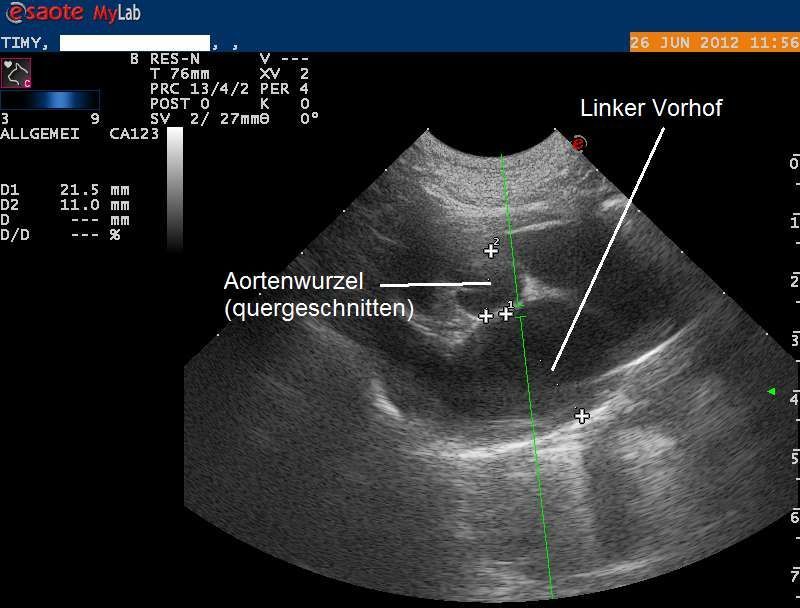

Die Röntgenbilder weisen auf eine Herzerkrankung hin, welche zum Verschluss der Körperschlagader geführt haben könnte. Das Herz wird mittels Ultraschall genauer untersucht, und es zeigt sich, dass die Muskulatur der Herzkammern sehr stark verdickt und die Vorhöfe stark erweitert sind. Eine Diagnose einer Hypertrophen Kardiomyopathie (HCM) wird gestellt.